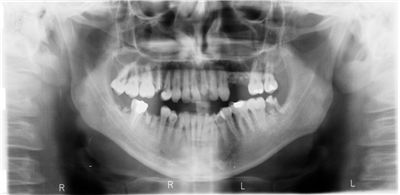

Dentistry is one of the major branches of medicine. Its focus is on oral cavity, and studies, diagnoses, prevents and treats its diseases, disorders and conditions. Dentistry is practiced by doctors called dentists. Persons that also provide oral health services are dental assistants, dental hygienists, dental technicians, and dental therapists.